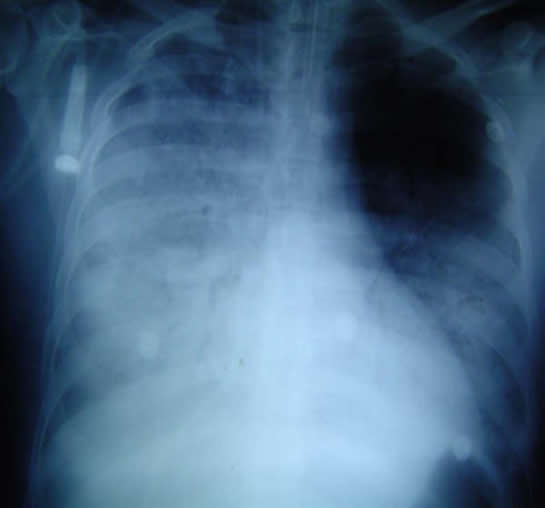

Gripe A H1N1 (Gripe Porcina) y Homeopatía

Gripe A y Homeopatia

PREHGRIP PREVENTIVO HOMEOPATICO DE LA GRIPE A